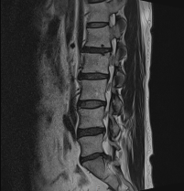

그림4.png 촬영 일시: 2025.01.23

<Fig 1. 요추 MRI>

MRI 결과가 보여준 실체

요추 4-5번, 5번-천추1번 사이의 디스크 탈출

중심부 및 우측 신경 협착

근전도 검사에서 탈수초화된 요추 신경병증 확인

이 결과를 보면서 저는 말씀드렸습니다.

"지금까지 왜 이렇게 아프셨는지 이제 명확해졌네요.

다행히 수술까지 할 정도는 아니지만,

제대로 된 치료를 받지 않으면

앞으로 더 심해질 수 있는 상태입니다."

4️⃣ 4개월 후: 재검 MRI에서 협착 현저히 감소 확인

특히 4개월 후 재검 MRI 결과를 보면서

저도 깜짝 놀랐습니다.

신경 협착이 확연히 줄어든 것이

영상으로도 명확히 보였거든요.